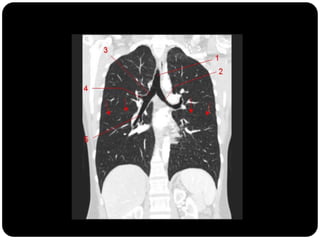

Traquéia       Brônquios principais originam-se da traquéia

Brônquios –     na carina;

PRINCIPAIS

LOBARES

Bronquíolos    Brônquio direito: ângulo mais obtuso com o

Alvéolos        eixo longo da traquéia;

 Direito(2,2cm) mais curto que o

esquerdo(5cm);

Traquéia      BPD:   BLSD

Brônquios –

BI - BLM

LOBARES              BI – BLID

Bronquíolos

Alvéolos

BPE:   BLSE

BLIE

No pulmão esquerdo

AP AM

JUNTA:

APICOPOSTERIOR

ANTEROMEDIAL basal

Esquerdo



Pulmão direito

Superior: direito

Traquéia       Pulmão direito:

Brônquios           LSD: anterior, apical e posterior;

      LM: medial e lateral;

      LID: superior, basal medial, basal lateral,

basal anterior, basal posterior;

 Pulmão esquerdo:

     LSE: apicoposterior, anterior,

superior(língula), inferior(língula);

     LIE: segmento superior, basal antero-

medial, basal lateral e basal posterior;